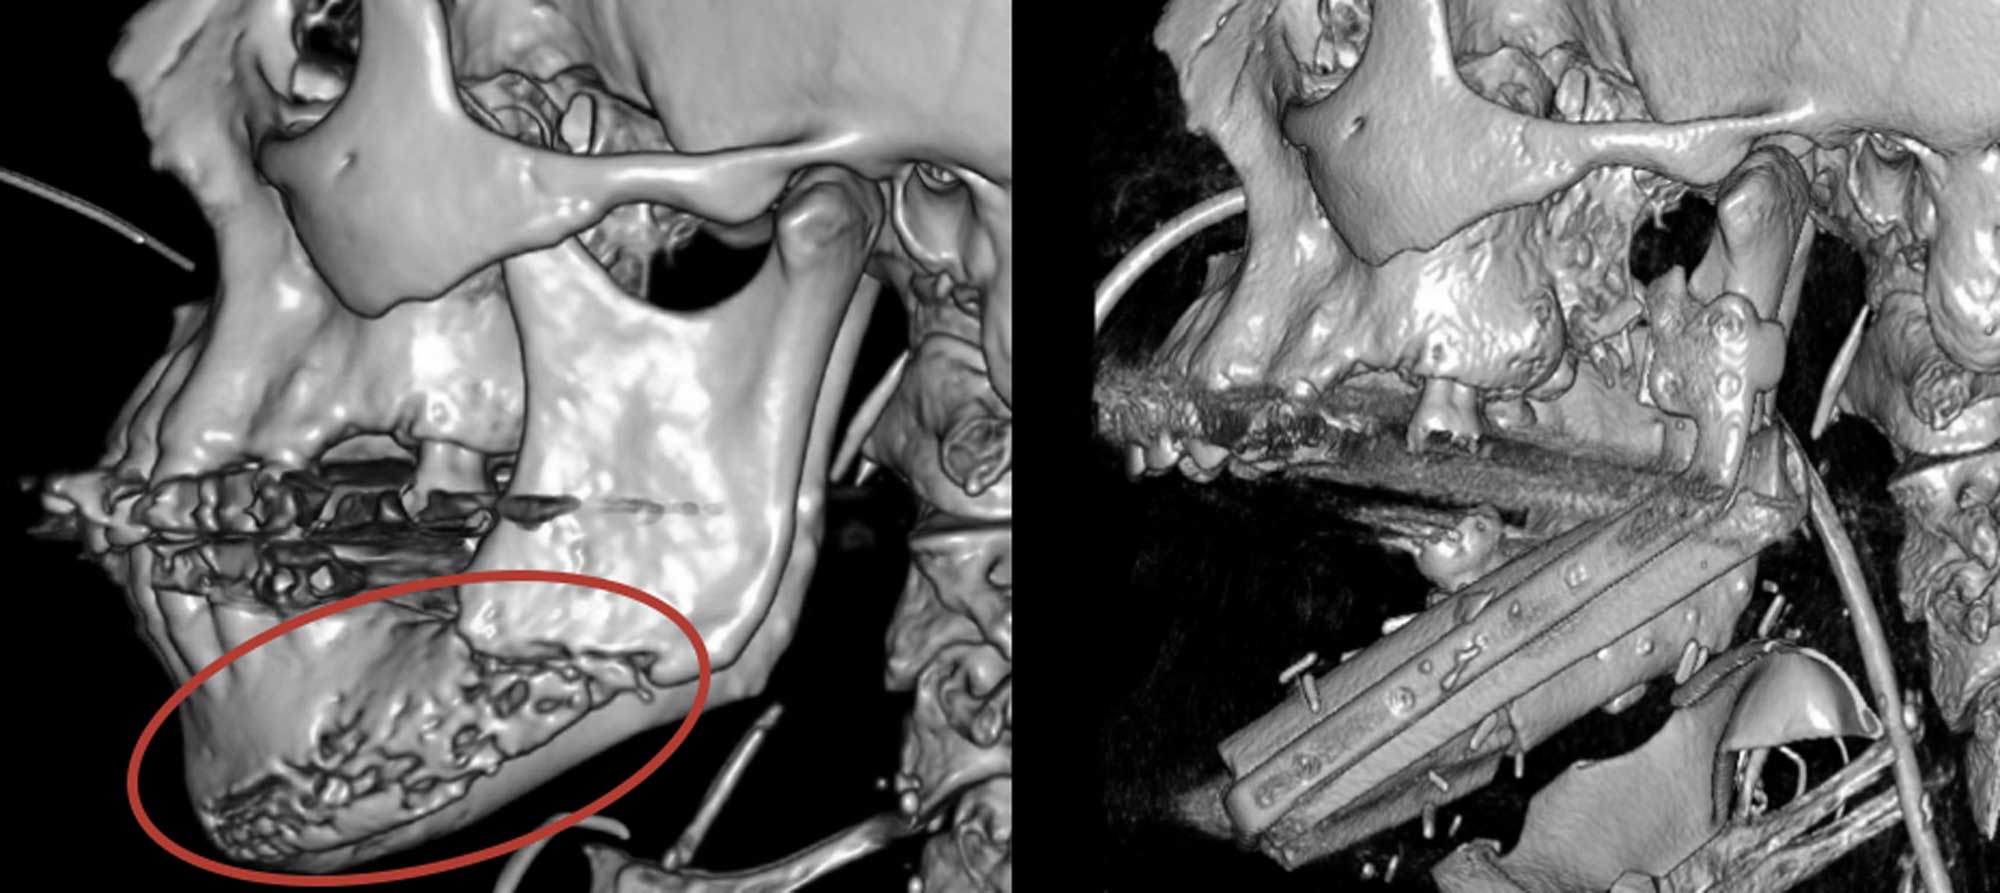

Left, a pre-surgical CT scan shows Roger Floyd’s jawbone with substantial radiation necrosis. Right, a post-surgical CT scan shows Roger Floyd’s jaw after it was replaced with a titanium plate and bone from his leg.

Then Dr. Hechler teamed up with Duke plastic surgeon Detlev Erdmann, MD to create a detailed surgical plan. Guided by specialized 3D CT scans and custom cutting guides, Dr. Erdmann removed Floyd’s fibula bone -- a non-weight-bearing bone in his lower leg -- and shaped it to match the mandible. After Dr. Hechler removed about 60% of Floyd’s jawbone, he and Dr. Erdmann replaced it with a new, healthy bone along with a customized titanium plate for stability. To keep the new bone healthy and allow it to grow, they attached blood vessels from the harvested bone to vessels in Floyd’s neck. Floyd went home about six days after the eight-hour surgery.